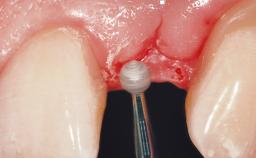

Late Placement of an Implant in a Maxillary Left Central Incisor Site

A 36-year-old female patient was referred for the replacement of the upper left central incisor (tooth 21), which had fractured. Although the tooth had been asymptomatic for many years, the crown began to loosen, at which time she presented to her dentist for an assessment. Teeth 21 and 22 had both been endodontically treated many years previously. She was a healthy individual and a non-smoker.

On examination, the patient had a low lip line and only displayed the coronal half of the anterior teeth when smiling.

The crown of tooth 21 was splinted to the adjacent teeth with composite resin, and the gingiva was inflamed.